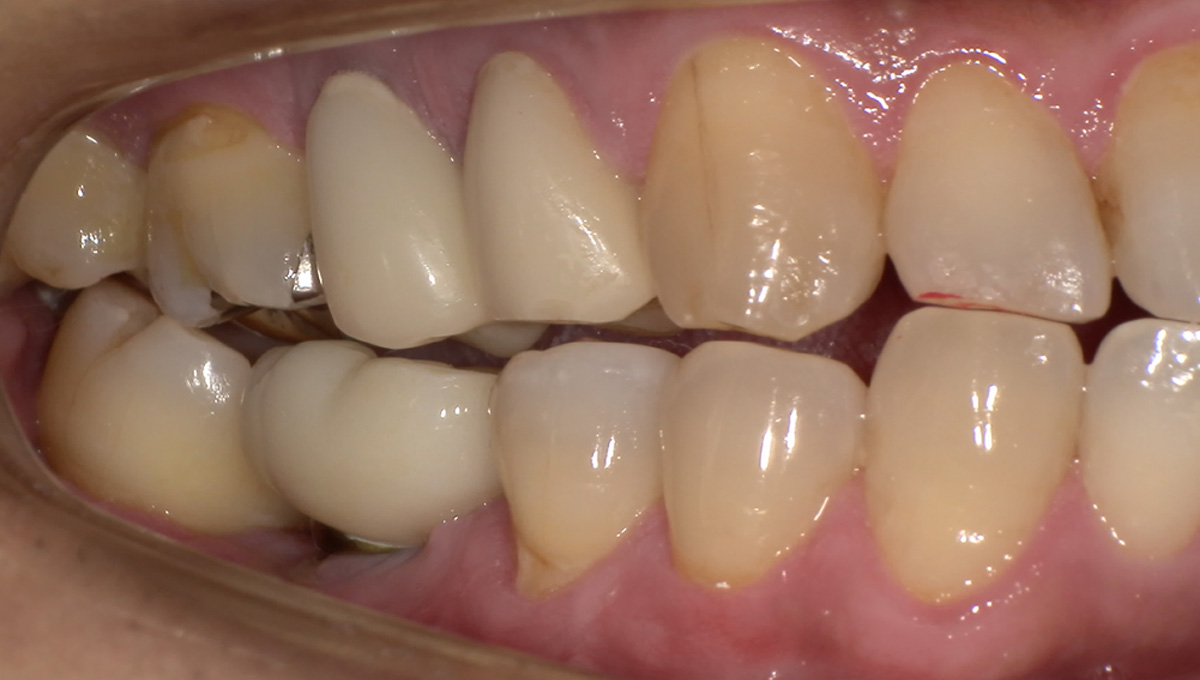

初診時

歯が割れていて、痛みがあり、抜歯となりました。